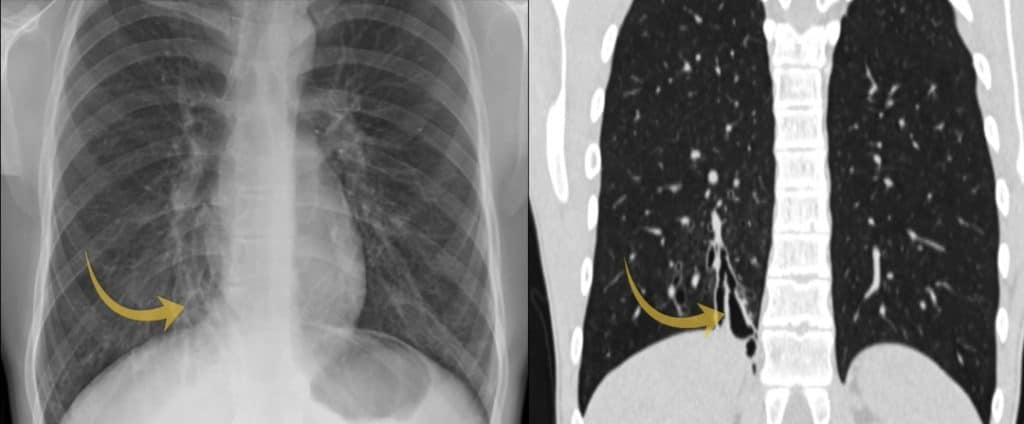

A man in his 20s attends his GP after struggling with recurrent chest infections. A chest X-ray is performed—do you see anything abnormal? This is a tricky one.

PA view of a chest X-Ray of a male in his 20s

We can see the area of lung by the right heart border looks abnormal and if you look closely you can just make out a ‘ring shadow’. Ring shadows on a chest X-ray raise the possibility of bronchiectasis.

Compare the area of lung adjacent to the right (yellow arrow) and left heart border (white arrow) and you will see the region adjacent to the right heart border appears abnormal. Look closely and you will see a ‘ring shadow’ raising the possibility of bronchiectasis.

Now that we’ve analysed the CT, let’s go back to the original chest X-ray. The ring shadows represented dilated airways seen end-on and are something to look out for on X-Ray.

The area of abnormality on the chest X-Ray correlates with the area of cystic bronchiectasis seen on CT.